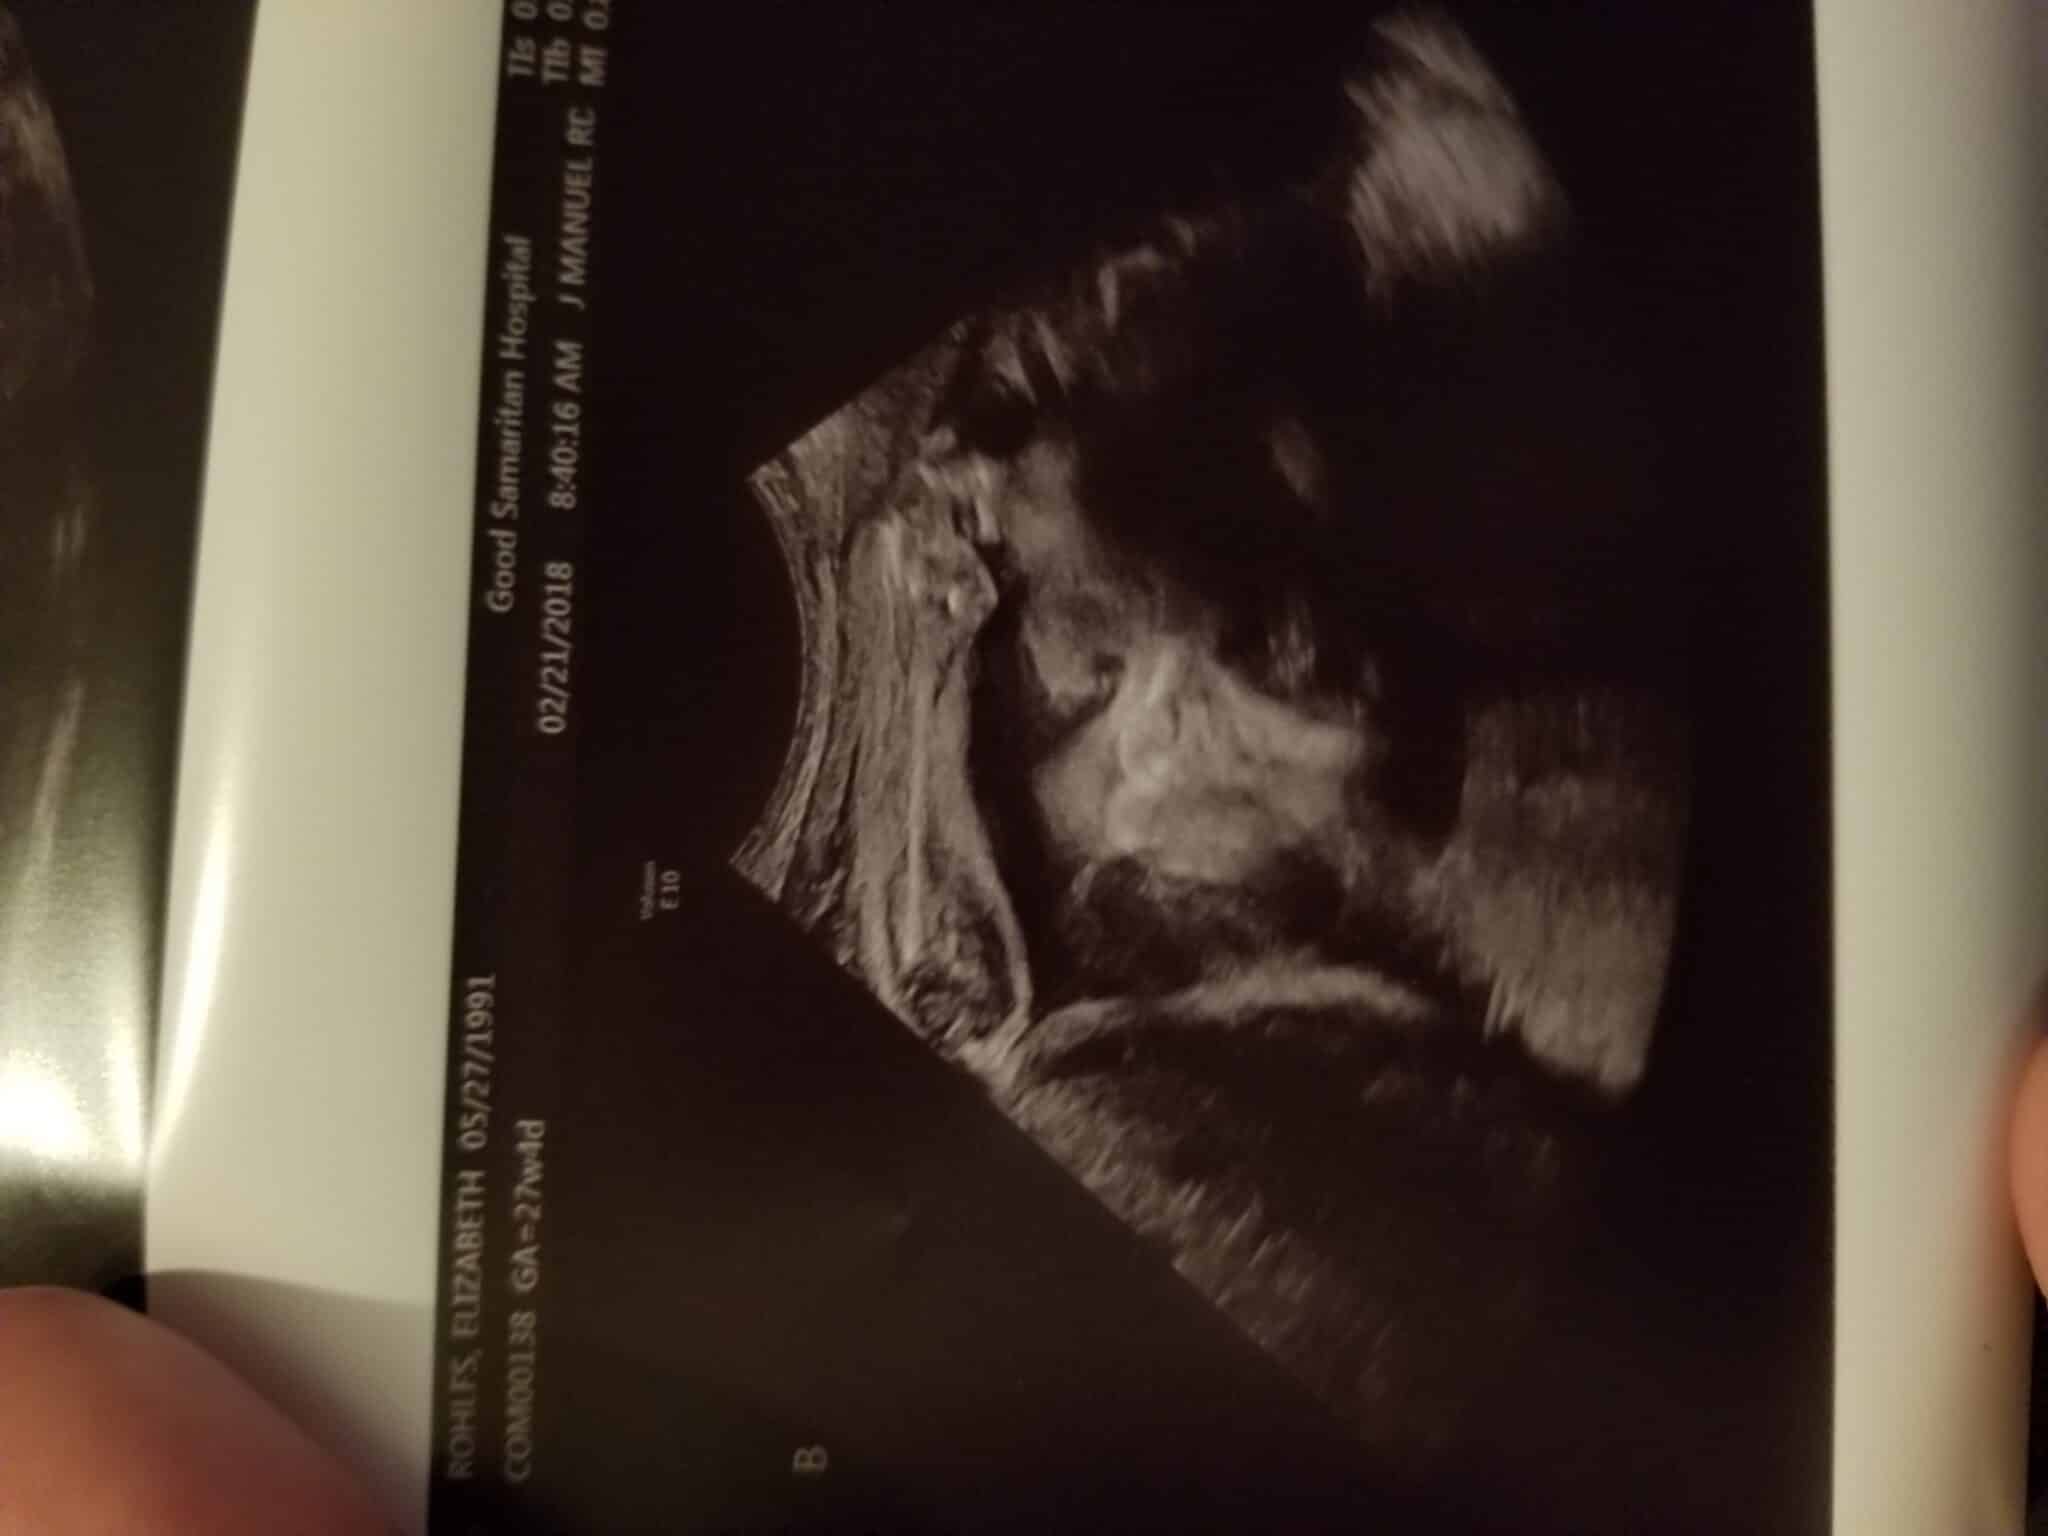

Ultrasound Photos at 27 Weeks Pregnant With Twins